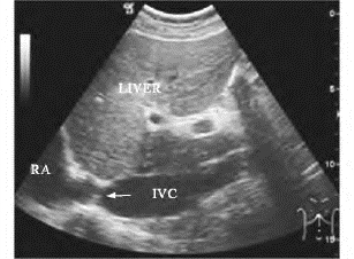

1.36.4四、腹腔大血管